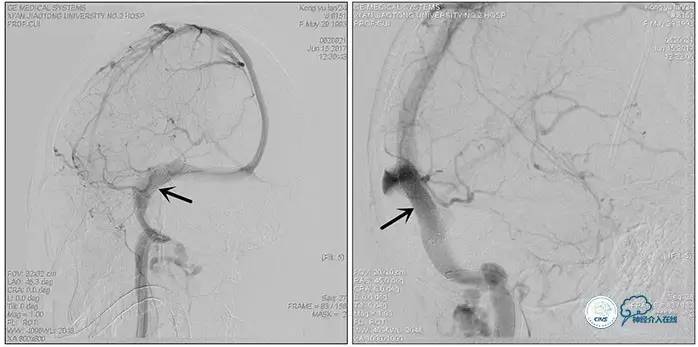

术中右侧ICA造影

右侧ICA斜位及窦内造影

右侧ICA斜位

窦内造影及路图

术中测压:

远端:520mmH2O,

近端:190mmH2O。

治疗方案:

1、8mm×40mm , EverCross球囊扩张;

2、8mm×40mm,Protégé自膨支架成形术。

术后右侧ICA造影

术后远、近端压力差为:0

术后右侧ICA斜位